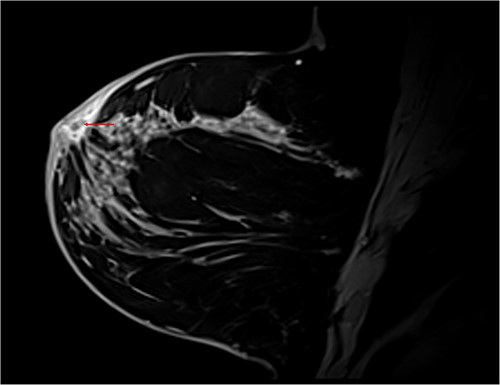

T1 Dixon sagittal MRI of the breast—changes restricted to the skin. Diffuse skin thickening of the periareolar region with small fluid collections (red arrow).